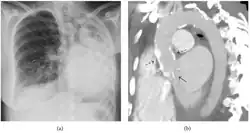

El diagnóstico del fibrotórax suele basarse en una historia clínica adecuada combinada con técnicas de imagen como la radiografía de tórax o la tomografía computarizada.[3] Estas herramientas detectan el engrosamiento pleural y la fibrosis alrededor de los pulmones.[7] La presencia de una corteza engrosada, con o sin calcificación, es una característica común en las imágenes.[3] Las tomografías computarizadas diferencian mejor si el engrosamiento se debe a depósitos de grasa o a fibrosis verdadera.[3]

En casos graves, el pulmón afectado puede perder volumen[7] y el mediastino puede desplazarse hacia el lado afectado.[3] Una reducción del tamaño de un lado del tórax en las imágenes sugiere cicatrización crónica.[6] Los signos de la enfermedad subyacente que causa el fibrotórax también se observan ocasionalmente en la radiografía.[6] Las pruebas de función pulmonar suelen mostrar hallazgos compatibles con una enfermedad pulmonar restrictiva.[6]

Fibrotórax extenso en el lado izquierdo. -

Radiografía de tórax que muestra opacidad heterogénea en la mitad izquierda del tórax por fibrotórax. -

Radiografía de tórax (izquierda) y tomografía computarizada (derecha) que muestran fibrotórax. -